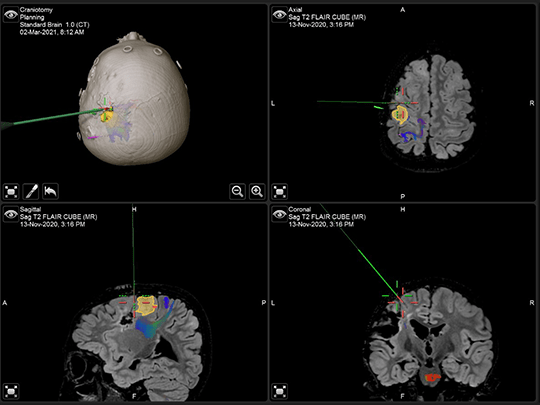

“We map the networks of the brain that are causing seizures and then map the networks of the brain that are functionally important,” explained Dr. Greiner. “Then we work with our colleagues in the Epilepsy Center, including neuroradiology and, obviously, neurosurgery, to develop a plan of attack.”

In an effort to remove the specific area of the brain that was causing Aiden’s seizures, the surgical team, led by neurosurgeon Francesco T. Mangano, DO, performed resection surgery in March 2021.

“Our goal is to be as minimally invasive as possible and remove as little brain tissue as might be necessary,” explained Dr. Mangano. “[Aiden’s] plan involved a fairly small tuber resection in the left frontal lobe, which was promising. Unfortunately, the location was very close to his motor system—the part of his brain that controls his right-sided movements.

“This was challenging, but our team provided Dr. Mangano with the functional maps generated from [Aiden’s] evaluation, and he did a wonderful job removing the target tuber without affecting the nearby motor system,” said Dr. Greiner.